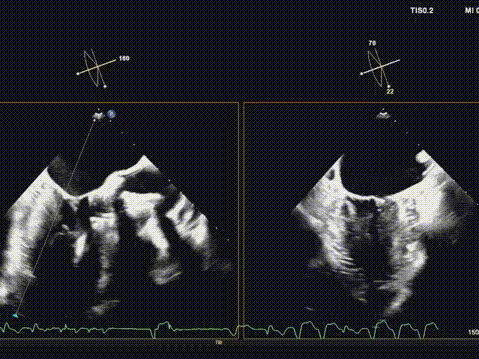

术后超声评估,瓣膜位置深度满意,形态可,微量瓣周漏,最大血流速度1.53m/s,平均跨瓣压差4mmHg。

华正东教授在术后总结中指出,全超声引导TAVR技术在避免放射线及造影剂相关肾损伤方面具有独特优势,特别适用于合并肾功能不全的高危患者。在本例手术中,超声影像清晰引导了导丝跨瓣、球囊预扩、瓣膜输送与释放等关键步骤,展现了其在复杂解剖条件下实现精准介入的可靠性。

术后超声提示人工瓣膜功能良好,平均跨瓣压差仅4mmHg,血流动力学改善显著。值得一提的是,术中选用的Evolut PRO瓣膜系统凭借其可回收、可重新定位的设计特点,为术中调整释放位置提供了重要技术支持,确保了瓣膜的稳定锚定与功能良好。此例手术的成功,充分展现了全超声引导TAVR在治疗二叶式主动脉瓣狭窄方面的可行性与安全性,为华中地区开展绿色介入技术积累了宝贵经验。